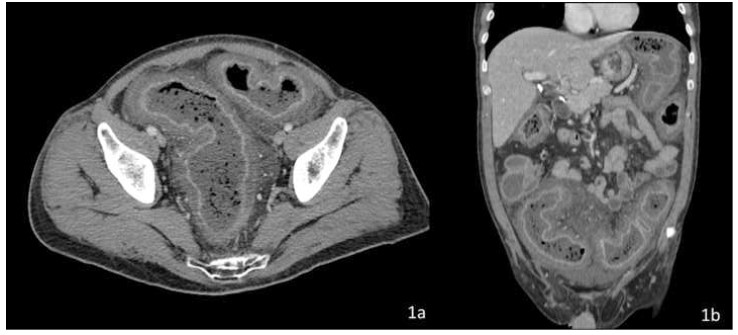

Computed tomography (CT) with IV and oral contrast revealed severe, diffuse colonic wall thickening, pericolic fat stranding and marked enhancement of the colic mucosa and submucosa secondary to hyperemia (Figure 1).

Figure 1: Axial (a) and sagittal (b) plane of CT scan showing dilated colon with wall thickening and inflamed mucosa.